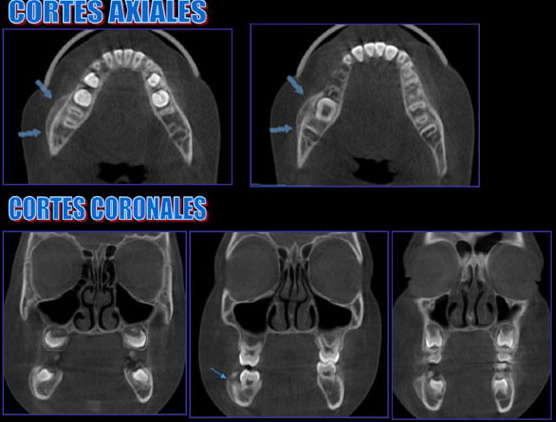

Paciente masculino 8 años de edad, es referido a la consulta para la evaluación con tomografía volumétrica por presentar un aumento de volumen indurado en la zona molar inferior derecha. En la radiografía panorámica notamos la ausencia de la piezas 8.4, 8.5 y la pieza 4.6 en infraoclusión. Se realiza estudio con tomografía volumétrica (Picasso E-WOO), se grafican cortes axiales, coronales y transaxiales que muestran a nivel de la pieza 4.6 ensanchamiento del espacio pericoronario hacia vestibular y reacción periostal que se extiende hacia la pieza 4.5 y 4.7.

Las infecciones odontogénicas tienen dos orígenes principales como son: periapical como resultado de una necrosis pulpar y periodontal como resultado de una bolsa profunda que permita la inoculación bacteriana. La osteomielitis es la inflamación de todas las estructuras del hueso: médula, corteza, periostio, vasos sanguíneos y nervios. En niños o adultos jóvenes pueden conllevar a la elevación del periostio y a la formación de hueso nuevo, resultando una osteomielitis con periostitis proliferativa como el presente caso relacionado a la erupción de la primera molar.